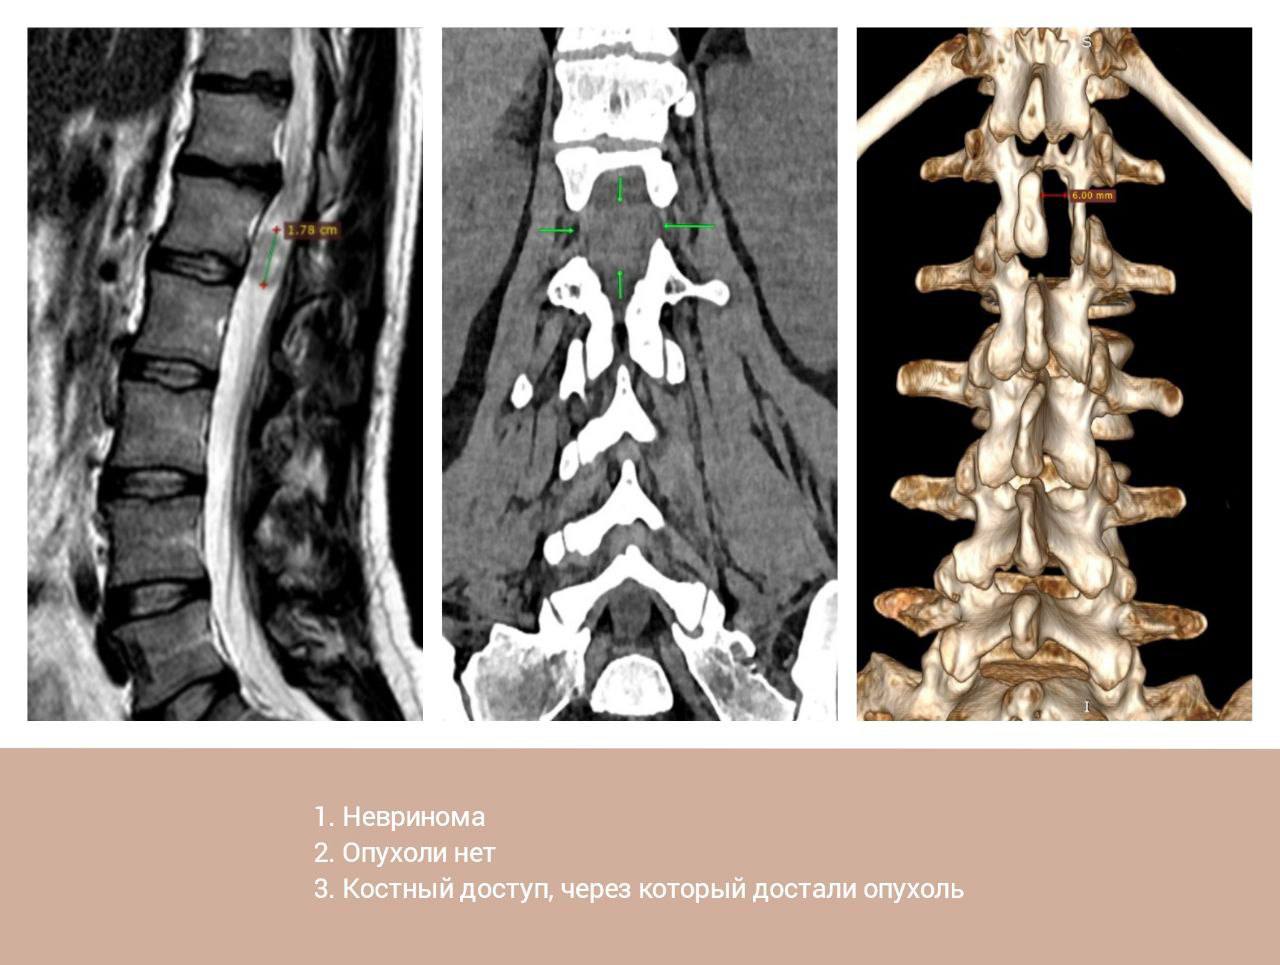

На МРТ врачи увидели 2-сантиметровое образование, которое сдавливало нервные окончания спинного мозга.

Опухолью оказалась спинальная невринома. Через очень маленький разрез медики удалили образование. Уже на следующий день после операции женщина смогла самостоятельно вставать, сидеть и двигаться.